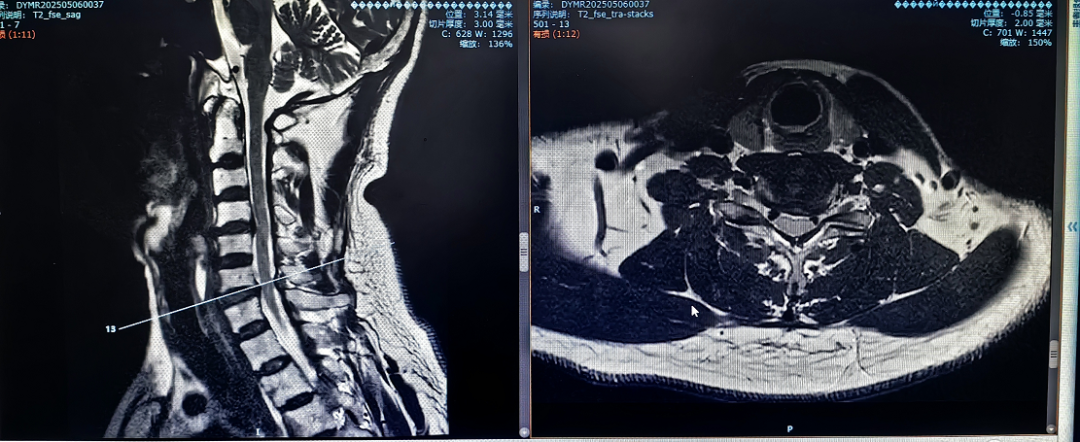

近日,貴陽市公共衛(wèi)生救治中心外三科骨科團隊在微創(chuàng)技術領域再獲突破,成功為一名56歲混合型頸椎病患者實施"頸椎間盤切除零切跡cage融合術"。該手術以創(chuàng)傷小、恢復快、穩(wěn)定性強的優(yōu)勢,標志著本院頸椎疾病診療邁入精準微創(chuàng)新階段。

患者因"頭痛、雙上肢麻木伴下肢乏力1月"入院,此前長期保守治療效果不佳,癥狀持續(xù)加重并出現(xiàn)行走不穩(wěn)。經(jīng)多學科聯(lián)合會診,團隊決定采用國際先進的零切跡cage融合術。手術歷時2小時,出血量僅10ml,術后患者即刻感到頸部及肢體癥狀顯著緩解,術后三天即可下床活動,微創(chuàng)切口(3—4厘米)及快速康復效果獲家屬高度贊譽。